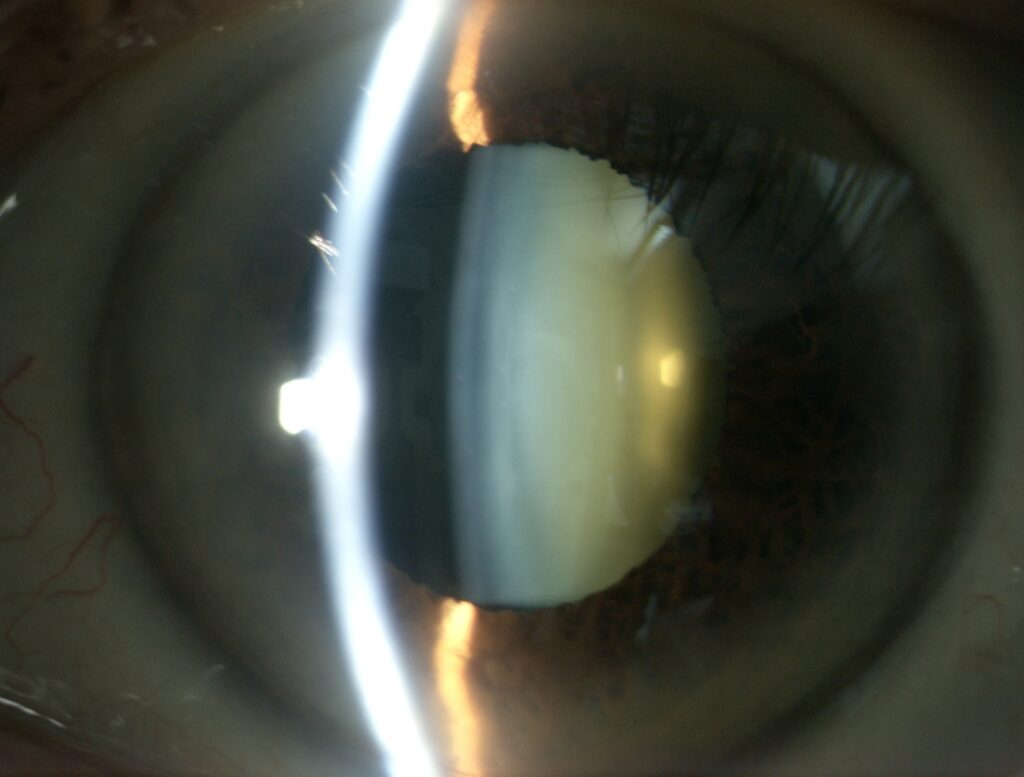

Valutazione e chirurgia della cataratta

L’opacità del cristallino è comune con l’avanzamento dell’età. In caso di suo riscontro, un intervento volto alla sua rimozione può permettere un miglioramento visivo.

Diagnosi e trattamento del cheratocono

Una volta considerata patologia rara, il cheratocono è una deformazione ectasica della cornea ed esordisce in adolescenza. Una diagnosi nello stadio precoce, assicura una strategia terapeutica efficace e non invasiva, grazie all’introduzione del cross-linking.

Chirurgia e trapianti di cornea

La rivoluzione dei trapianti lamellari ha permesso di ridurre l’invasività dell’intervento. Patologie come la distrofia di Fuchs, cheratocono avanzato ed esiti di cheratiti infettive oggi possono essere trattate favorevolmente con le nuove tecniche.